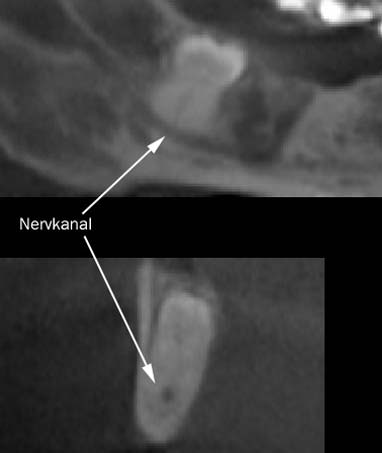

Hier verläuft der Nervkanal direkt durch den Weisheitszahn. Dieser Befund kann nur durch die zweite Ebene gesichert werden. Das DVT erlaubt eine sichere Diagnostik und hilft, sicher zu entscheiden.